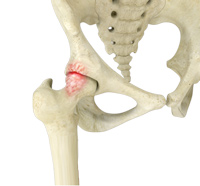

Osteoarthritis also called degenerative joint disease is the most common form of arthritis. It occurs most often in older people. This disease affects the tissue covering the ends of bones in a joint (cartilage). In a person with osteoarthritis, the cartilage becomes damaged and worn out causing pain, swelling, stiffness and restricted movement in the affected joint.

Inflammation of the joints is referred to as arthritis. The inflammation arises when the smooth covering (cartilage) at the end surfaces of the bones wears away. In some cases, the inflammation is caused when the lining of the joint becomes inflamed as part of an underlying systemic disease.